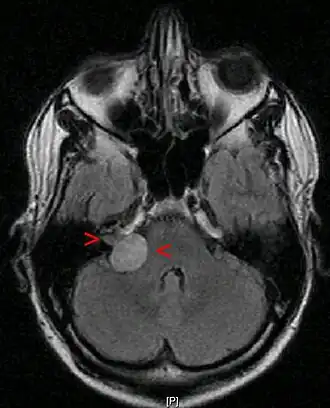

![]() Neurinoma acústico con un tamaño de 20 x 22 x 25 mm. RMN en corte axial a nivel de los globos oculares. | ||